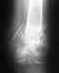

Здравствуйте! 31 августа 2010 г. попал в ДТП (мотоциклист). В итоге оскольчатый перелом н/3 со смещением обеих костей голени. Гематомы, некроз кожи в обл. перелома, жировая эмболия. Также были сломаны медиальный мыщелок, и межмыщелковое возвышение б/берцовой кости (на данный момент сросшиеся). Что касается голени, то результат виден на снимке - прошло 6,5 месяцев после травмы, и 4,5 месяца после операции (аппарат Илизарова). А теперь по порядку: при поступлении получил скелетное вытяжение, пробыл на нем около 2-х месяцев. За это время меня лечили от эмболии; делали репозицию; дренировали гематому в месте перелома (сначала разрезали скальпелем и вытащили основную часть гематомы, далее дренажные трубки); после созревания некроза (3х10 см) произведена некрэктомия, далее ждали грануляцию, потом аутопластика раны кожным лоскутом; после того как лоскут прижился была произведена операция (спустя 2 месяца с момента получения травмы) - чрезкостный остеосинтез методом Г.А.Илизарова.Сейчас прошло 4,5 месяца после операции - б/берцовая кость не сраслась, м/берцовая - тем более, даже не попадает отломками.Мужики, что делать? Мне 24 года, я люблю активный образ жизни и не хочу становиться калекой. Врач, который меня оперировал каждый раз говорит, что всё сростется и отправляет гулять ещё на 1,5 месяца. А с аппаратом Илизарова особо не погуляешь. Раньше ходил на костылях, теперь хожу с тросточкой с полной нагрузкой на травмированую ногу. Я понимаю, что нужно время, НО! за 4,5 ммесяца должна же образоваться костная мозоль, хоть какие-то признаки сращивания? А м/берцовая кость, что с ней делать (врач обещал, что непременно срастется - ошибся?!). Уважаемые врачи, специалисты, вы моя последняя надежда - жду ваших советов по поводу/методике дальнейшего лечения, а также прогнозов. Стоит ли ждать сращивания и ходить в аппарате, либо готовиться к операции и ставить интрамедуллярный штифт? С, уважением, Олег Иванов.